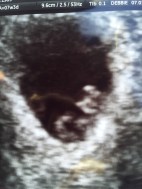

On the 7th January 2018, we first saw our little baby. The scan confirmed we were 7 weeks and 3 days pregnant and there on the screen was a little heart fluttering away. I breathed a sigh of relief. I felt like this was truly it! Everything tells you, once you have seen the heartbeat the chances of miscarriage were lowered.